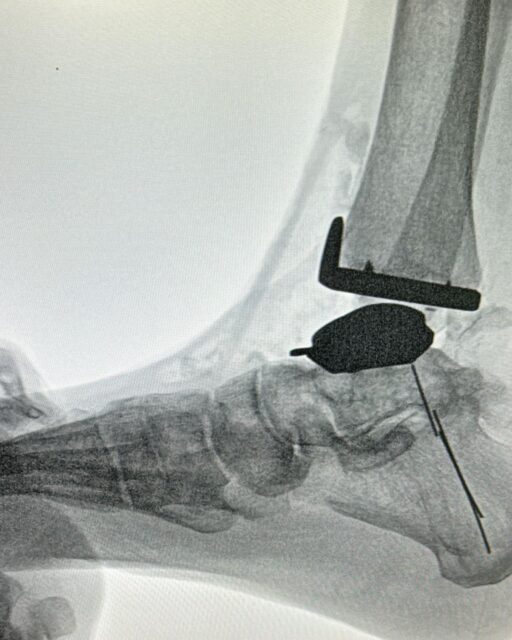

Cirugía ortopédica Reemplazo articular del tobillo

Reemplazo articular del tobillo

¿Sufre de dolor crónico en el tobillo? El reemplazo articular de tobillo podría ser la solución que busca. Este procedimiento quirúrgico consiste en sustituir la articulación dañada por una prótesis